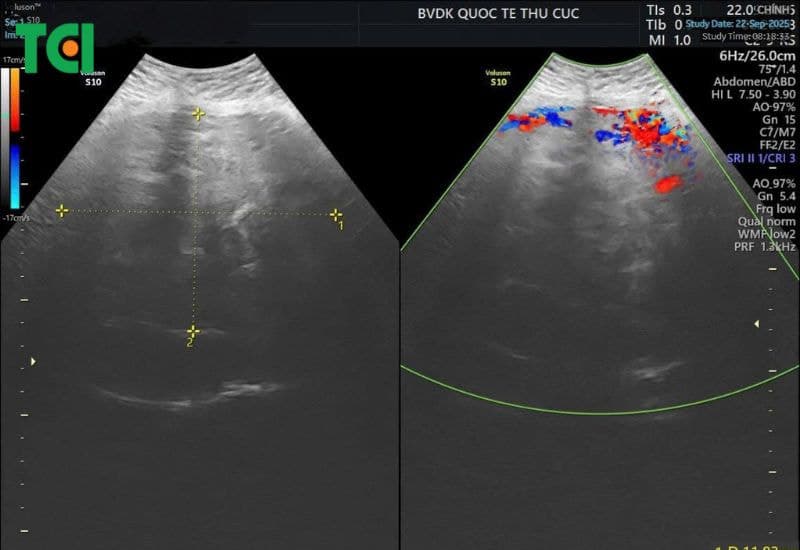

Hình ảnh cận lâm sàng cho thấy khối u “khổng lồ” vùng tiểu khung

Kết quả cận lâm sàng cho thấy mức độ nghiêm trọng của bệnh lý:

– Siêu âm phát hiện u xơ tử cung kích thước khoảng 118 x 94 x 194 mm.

– MRI tiểu khung cho hình ảnh khối u lớn, kích thước lên tới 99 x 176 x 212 mm, định hướng u xơ tử cung thuộc nhóm L6 theo phân loại FIGO 2018.

Theo phân loại FIGO, u xơ nhóm L6 thuộc nhóm u dưới thanh mạc, thường phát triển âm thầm, ít triệu chứng ở giai đoạn đầu nhưng khi đạt kích thước lớn có thể gây rong kinh, chèn ép và biến chứng nặng, khiến phẫu thuật trở nên khó khăn hơn

– Khối u kích thước rất lớn, tăng sinh mạch máu